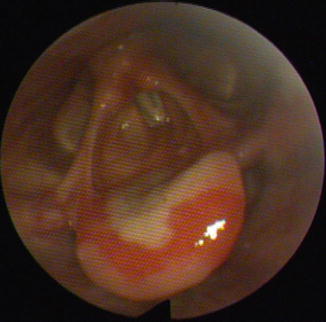

Fig. 35.9

Large fibrinous erosion surrounded by erythema on the laryngeal surface of the epiglottis